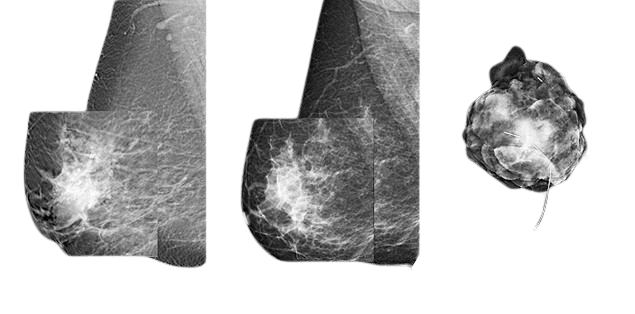

SELF-DEVELOPED IMAGE PROCESSING SOFTWARE

“Mammo IP”

It allows to see the smallest lesions from the breast tissue without losing sight of patients overall needs by applying Multi-scale local contrast enhancement technology.